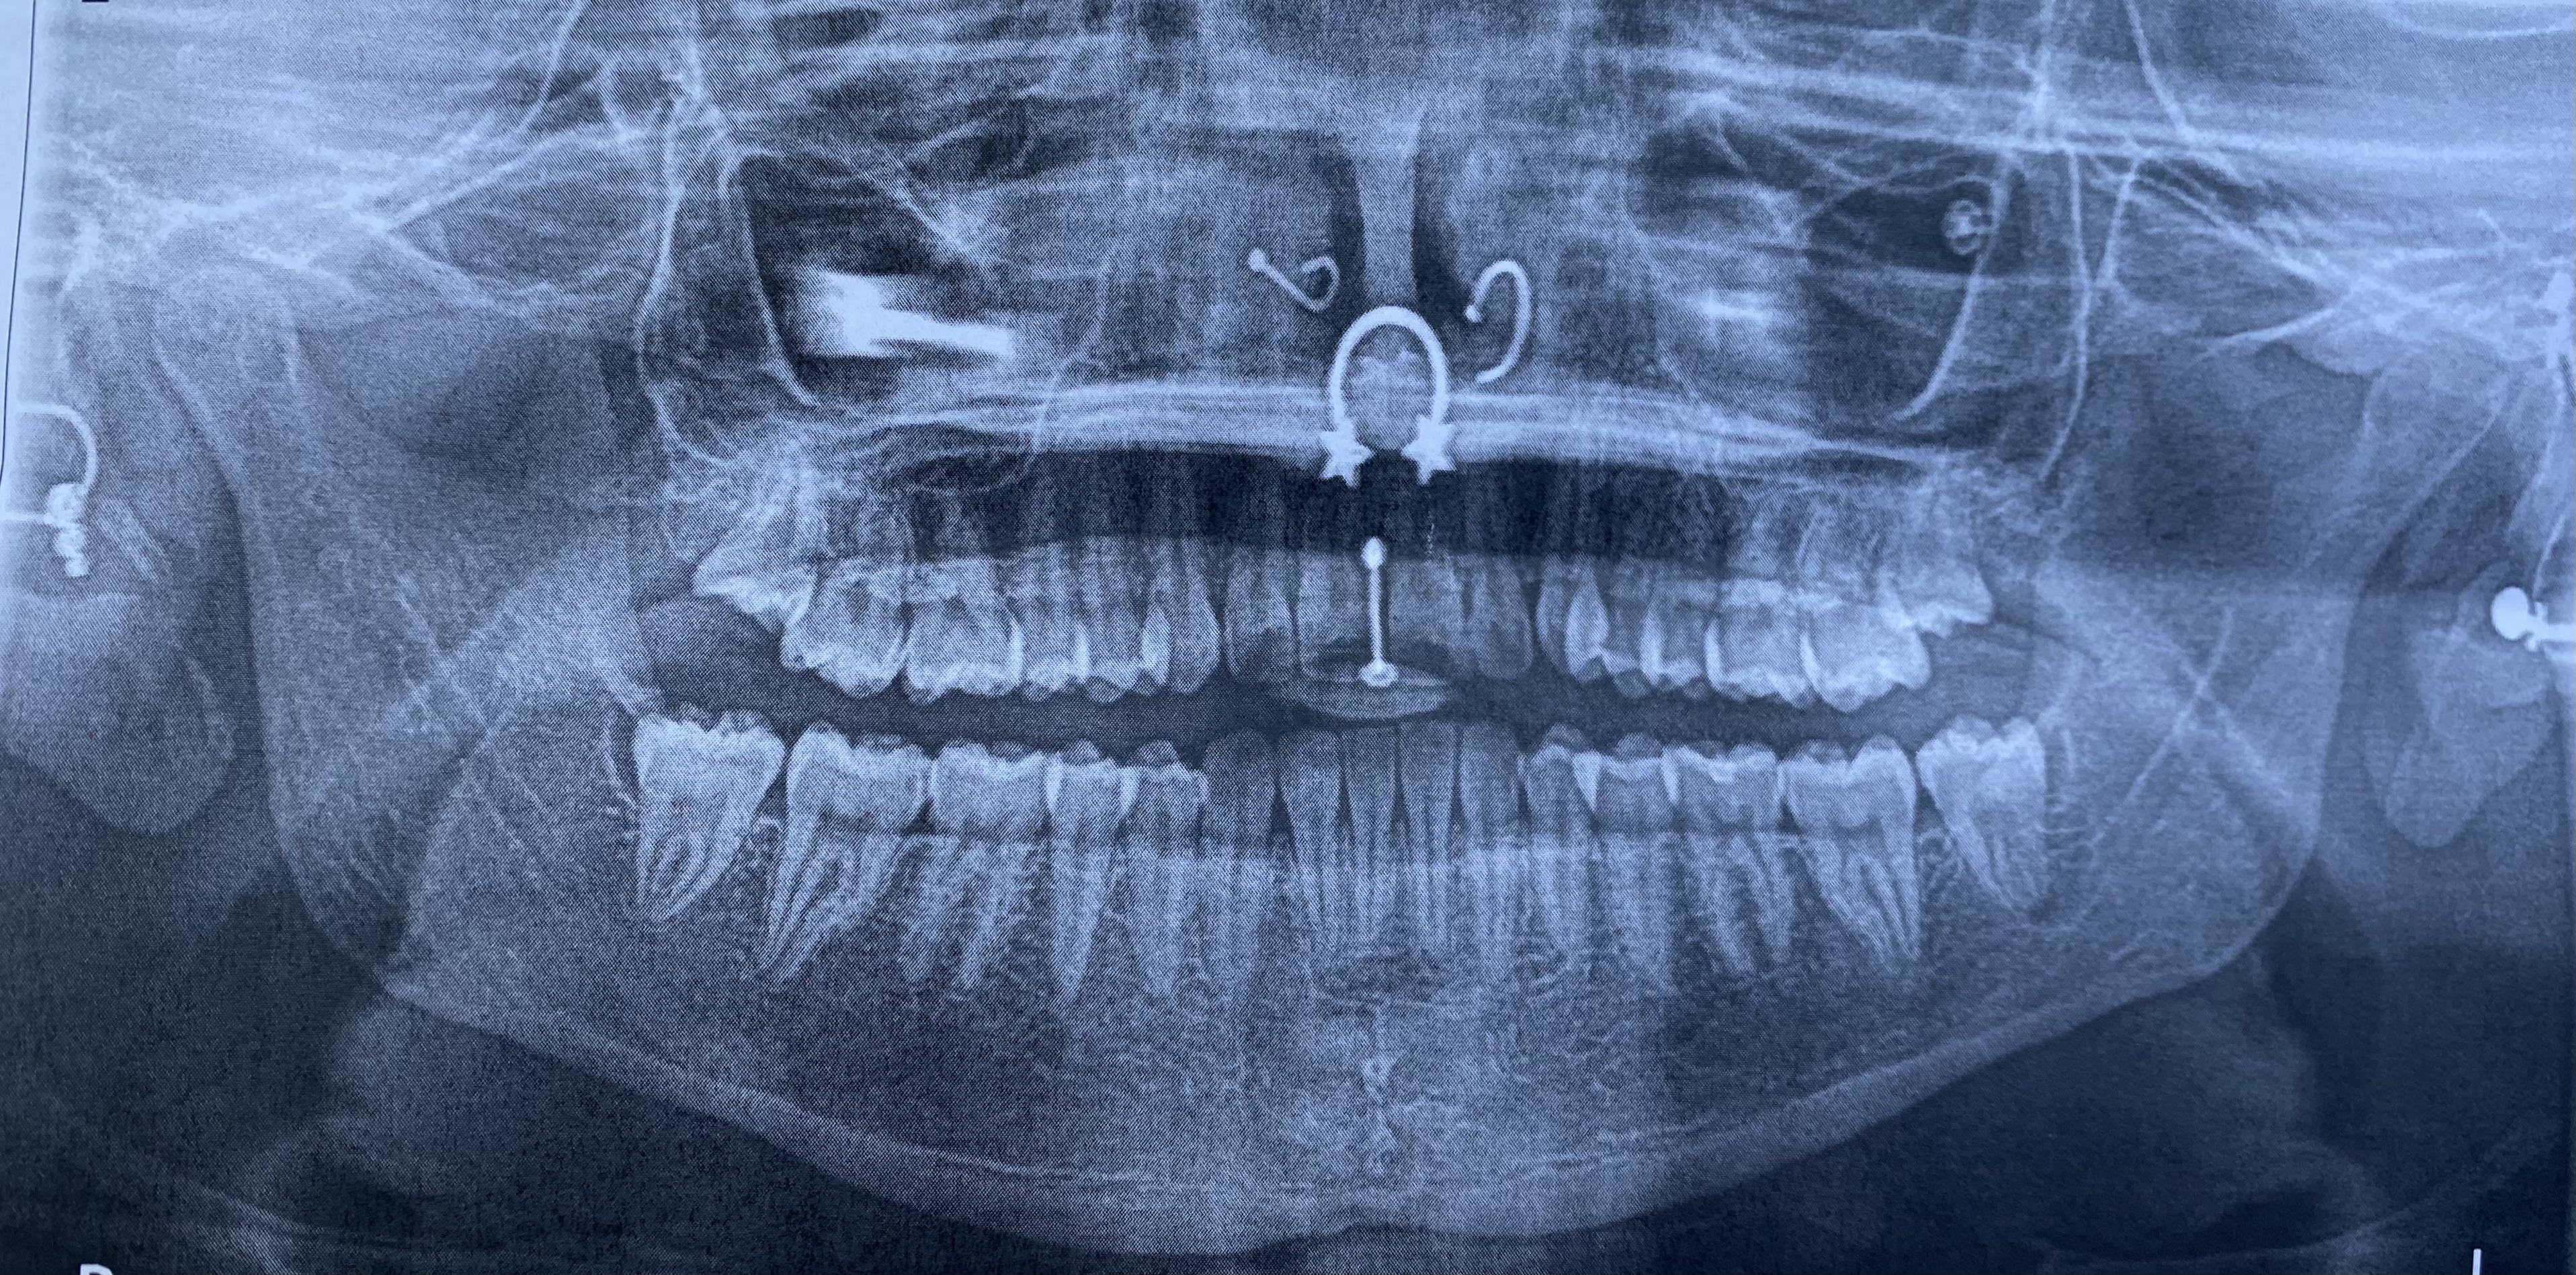

Piercings on display during dental Xray. They made me take my septum Dental X Rays And Piercings But what is a dental piercing? What are its effects on oral health, and are there any risks? By avoiding production of these artefacts when possible, we can reduce radiation exposure to patients while obtaining the most diagnostically. Tongue piercing results in dental and. Panoramic radiography is a commonly used imaging technique in radiology and may be a component of. Dental X Rays And Piercings.

got my first xray with all my piercings in taken at the orthodontist Dental X Rays And Piercings This image depicts the entire upper. What are its effects on oral health, and are there any risks? By avoiding production of these artefacts when possible, we can reduce radiation exposure to patients while obtaining the most diagnostically. But what is a dental piercing? Panoramic radiography is a commonly used imaging technique in radiology and may be a component of. Dental X Rays And Piercings.

Got my wisdom teeth out today. Peep the nose rings and all my ear Dental X Rays And Piercings Before deciding on an oral piercing, consider discussing it with your dentist beforehand. What are dental gems and piercing? By avoiding production of these artefacts when possible, we can reduce radiation exposure to patients while obtaining the most diagnostically. But what is a dental piercing? This image depicts the entire upper. Tongue piercing results in dental and. Panoramic radiography is. Dental X Rays And Piercings.

My dental Xrays featuring 3/4” lobes, helix and lobe, daith and Dental X Rays And Piercings This image depicts the entire upper. Tongue piercing results in dental and. By avoiding production of these artefacts when possible, we can reduce radiation exposure to patients while obtaining the most diagnostically. What are its effects on oral health, and are there any risks? What are dental gems and piercing? But what is a dental piercing? Panoramic radiography is a. Dental X Rays And Piercings.